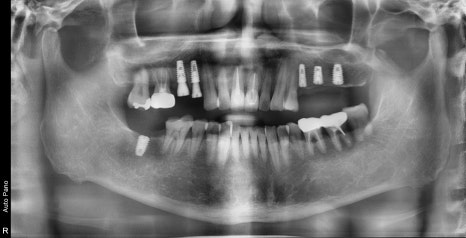

일단 가장 불편한 부위의 발치 및 임플란트 수술이 진행되었습니다.

발치 후 치아 상실 부위 임플란트 수술 후 사진입니다.

치아가 오랜 기간 없던 부위의 뼈 밀도가 낮아

충분한 시간을 기다리는 기간 동안

심한 마모에 의한 증상 있는 치아의 신경치료 및 보철 치료까지 완성을 했습니다.

임플란트 보철 완성 그리고, 교합력의 분산

비어있던 어금니 공간이 모두 회복이 되었습니다.